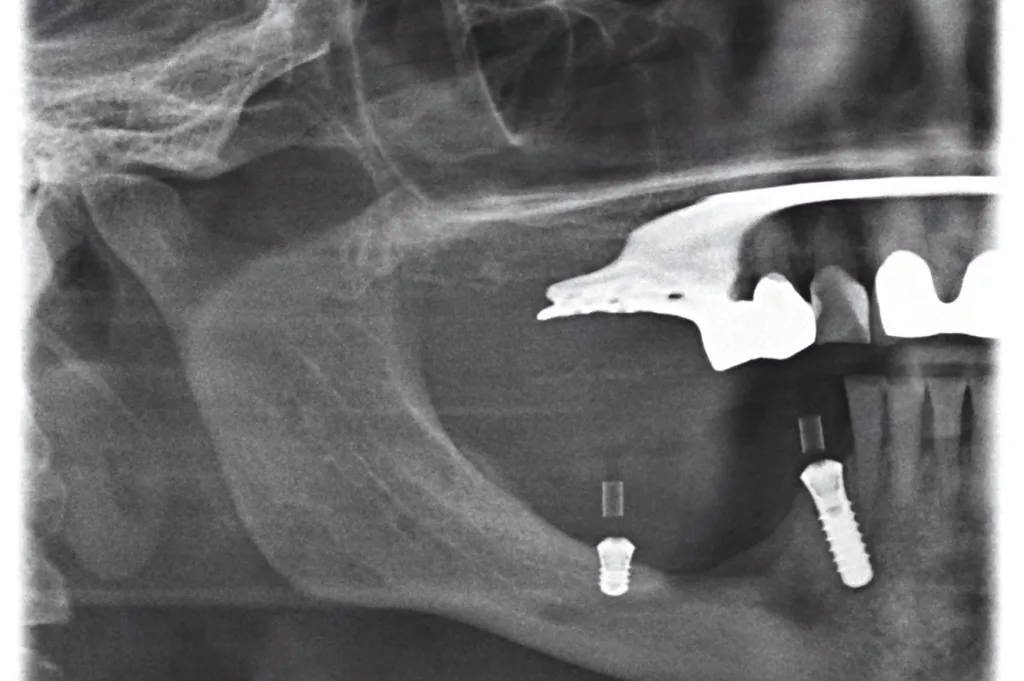

Im dritten Fall stellte sich eine Patientin nach Implantation alio loco und Implantatfraktur im vierten Quadranten vor. Zur Vorstellung zeigten sich rezidivierende Mundbodenabszesse. In zwei Schritten wurden die Implantate operativ entfernt. Anschließend wurden nach 3D-Knochenanalyse und angemessener Heilungsphase des Knochens offen ohne full guided Schablone zwei Implantate inseriert und mit einem teleskopierend abnehmbaren Zahnersatz prothetisch versorgt. Nach entsprechender DVT-Befundung konnte ein ausreichendes vertikales und horizontales Knochenangebot in regio 46 definiert werden. Eine 4 mm tiefe Implantatbettaufbereitung kann dann aus unserer Sicht freihändig erfolgen. Im Vorfeld wurde mit der Patientin auch die Möglichkeit eines Knochenaufbaus besprochen, der in diesem Fall wegen des ausgedehnten Volumenmangels mit Beckenkamm erfolgen hätte müssen. Im Hinblick auf Alter und Anamnese der Patientin fiel die Entscheidung nach Nutzen-Risiko-Analyse auf die Verwendung eines kurzen Implantates (Straumann, Regio 43 D 4,1 L 12, Regio 47 D 4,1 L4).